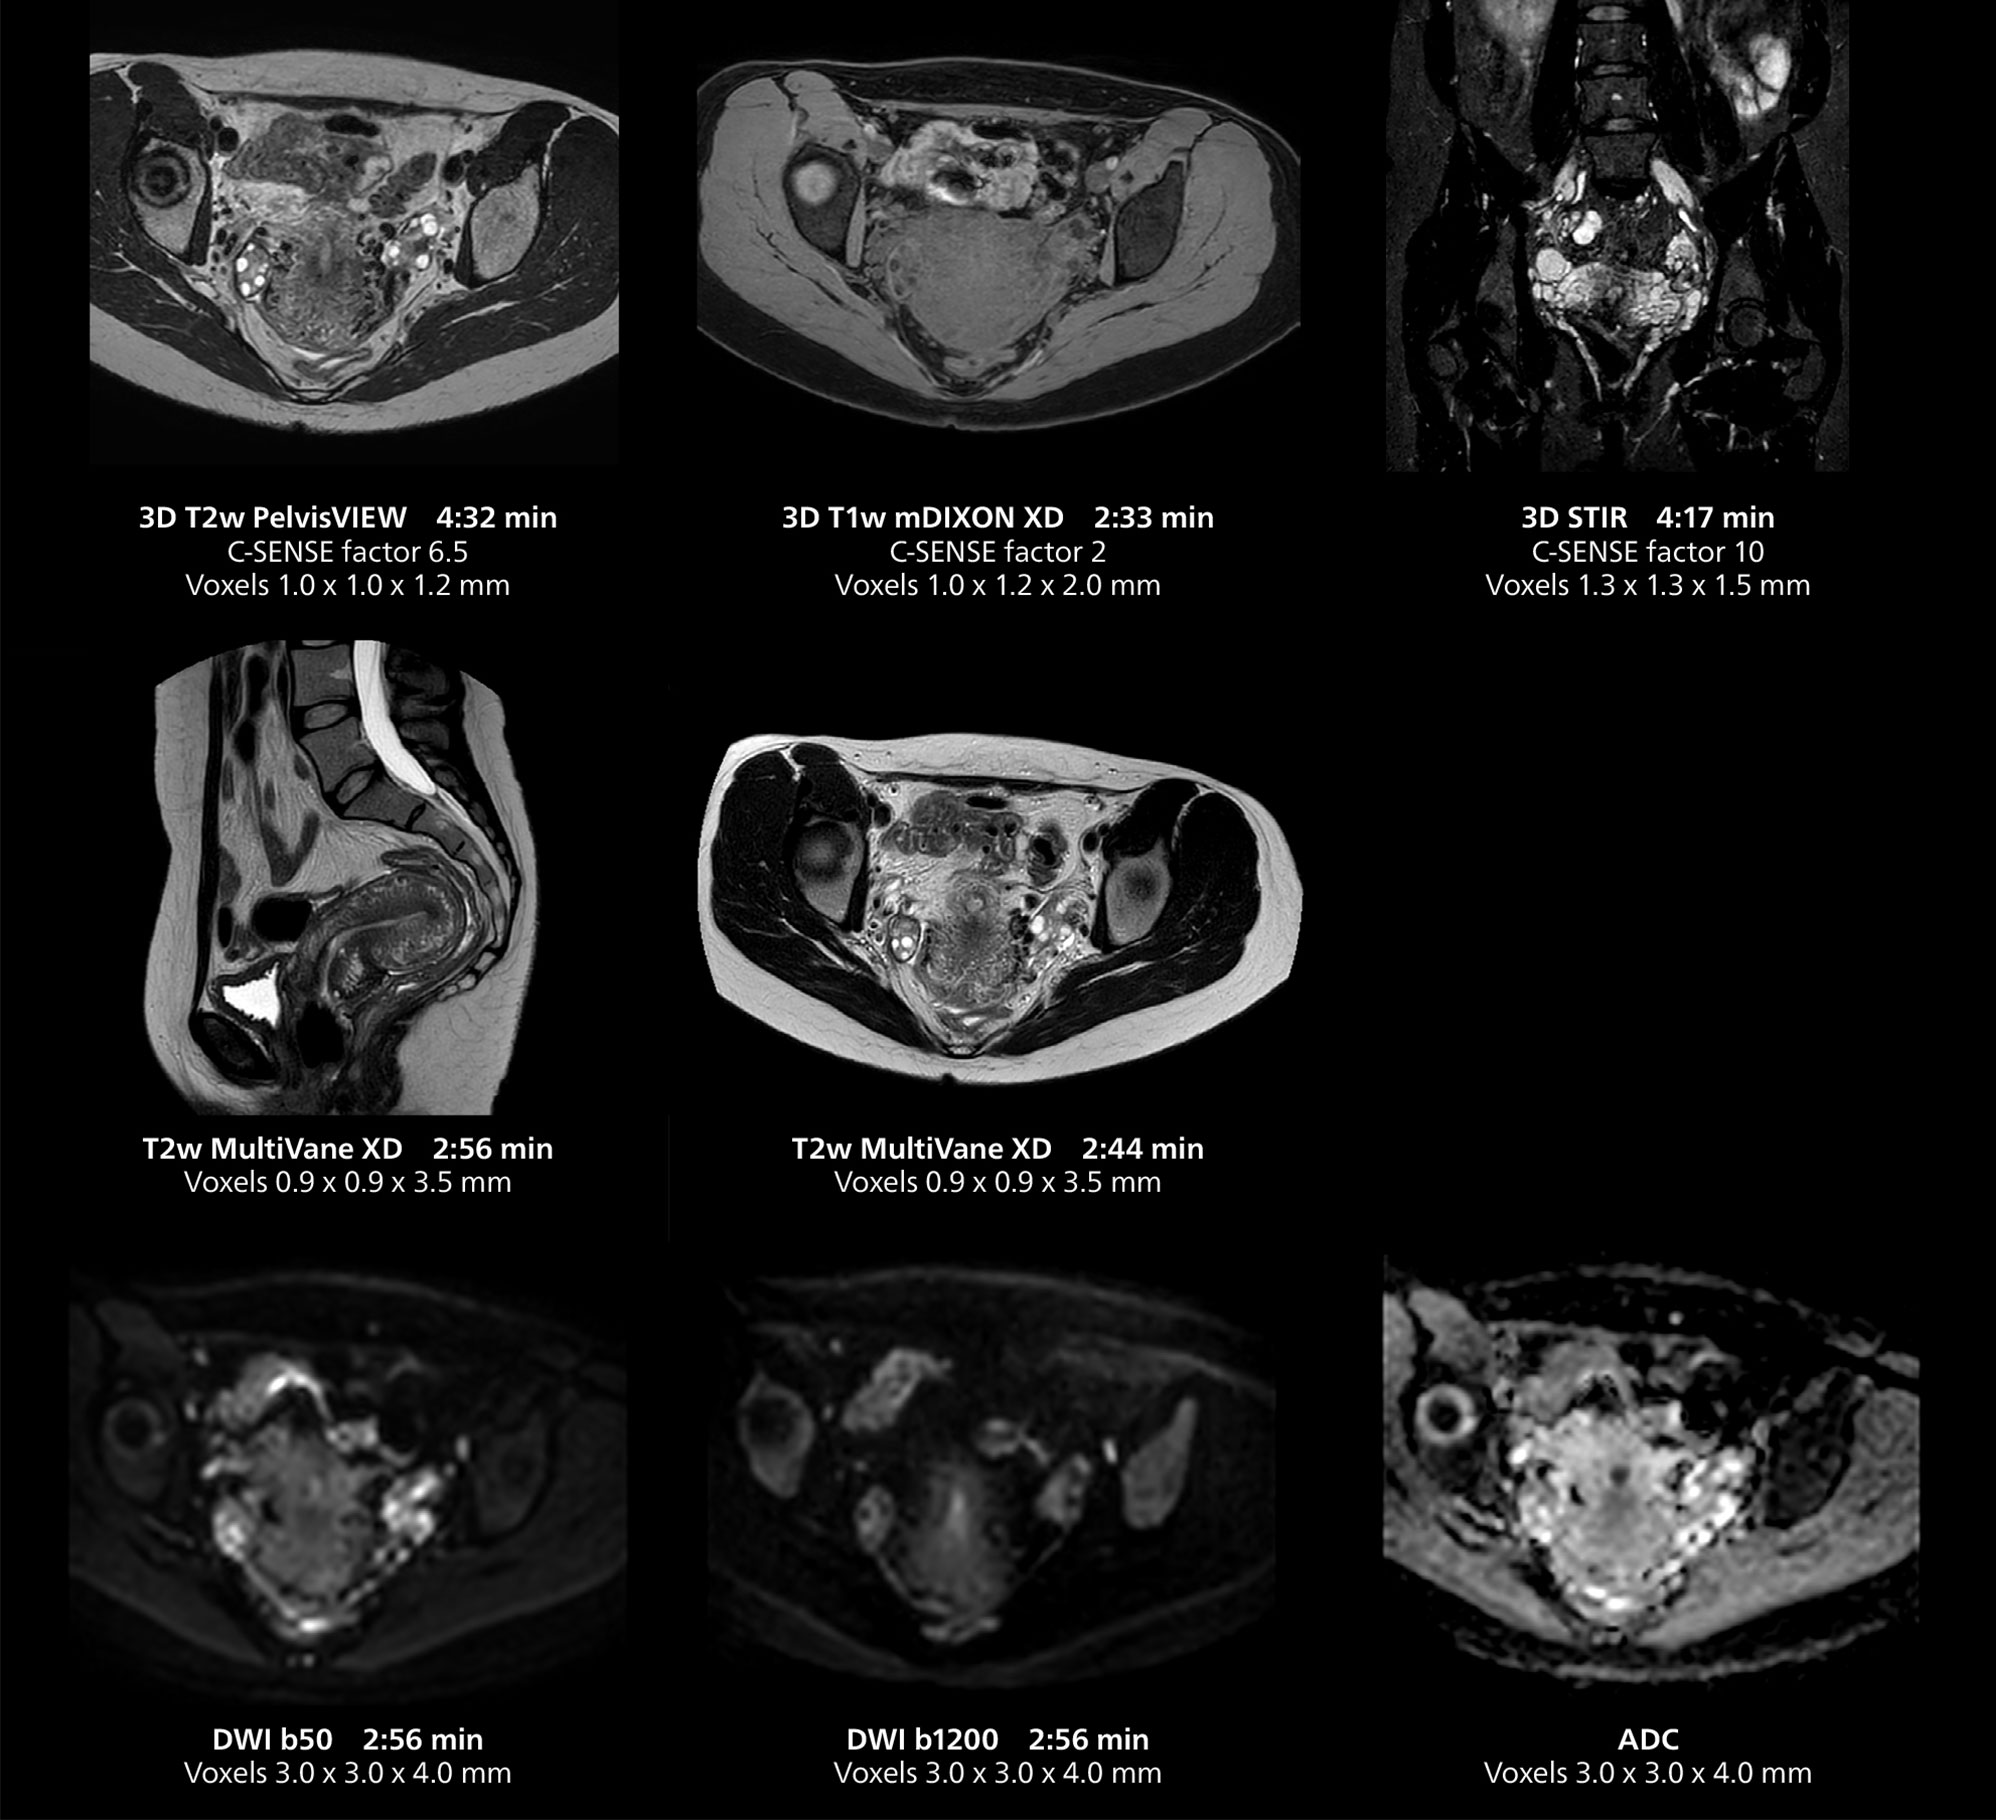

Female pelvis imaging

This MRI case illustrates good resolution and imaging quality obtained within reasonable scan times using the MR 5300 1.5T system with the anterior torso cardiac coil that allows use of a large field of view (FOV).

Female pelvis imaging

This MRI case illustrates good resolution and imaging quality obtained within reasonable scan times using the MR 5300 1.5T system with the anterior torso cardiac coil that allows use of a large field of view (FOV).

Free-breathing scans provide reproducibility and patient comfort

Dr. Gellée highlights the robust free-breathing scans as “the feature that makes the biggest difference in my daily work. The 3D free breathing sequences are very reproducible, and the axial acquisition is very good. For example, in endometriosis, which is one of my focus areas, it provides high contrast and good resolution so that I can see small details. We also use free breathing for liver and pancreas imaging. In multi-phase liver studies, 4D Free Breathing delivers 3-second temporal resolution, making a dynamic scan with more than one arterial phase possible.”

The MR 5300 with Compressed SENSE is up to 50%** faster for many exams. It can provide routine exams in less than 5 minutes and whole-body exams in less than 20 minutes. Saint-Augustin has taken advantage of that speed to create highly efficient protocols. The hospital’s standard stroke protocol is just about 8 minutes, and standard ENT, prostate PIRADS staging, and endometriosis studies all clock in at just about 10 minutes.***

“We have more speed in 3D sequences,” Dr. Gellée states. “With Compressed SENSE, we can replace two or three 2D scans withone high-quality 3D scan. High quality additional orientations are then obtained by post-processing of the 3D data set, thus saving scanning time.”